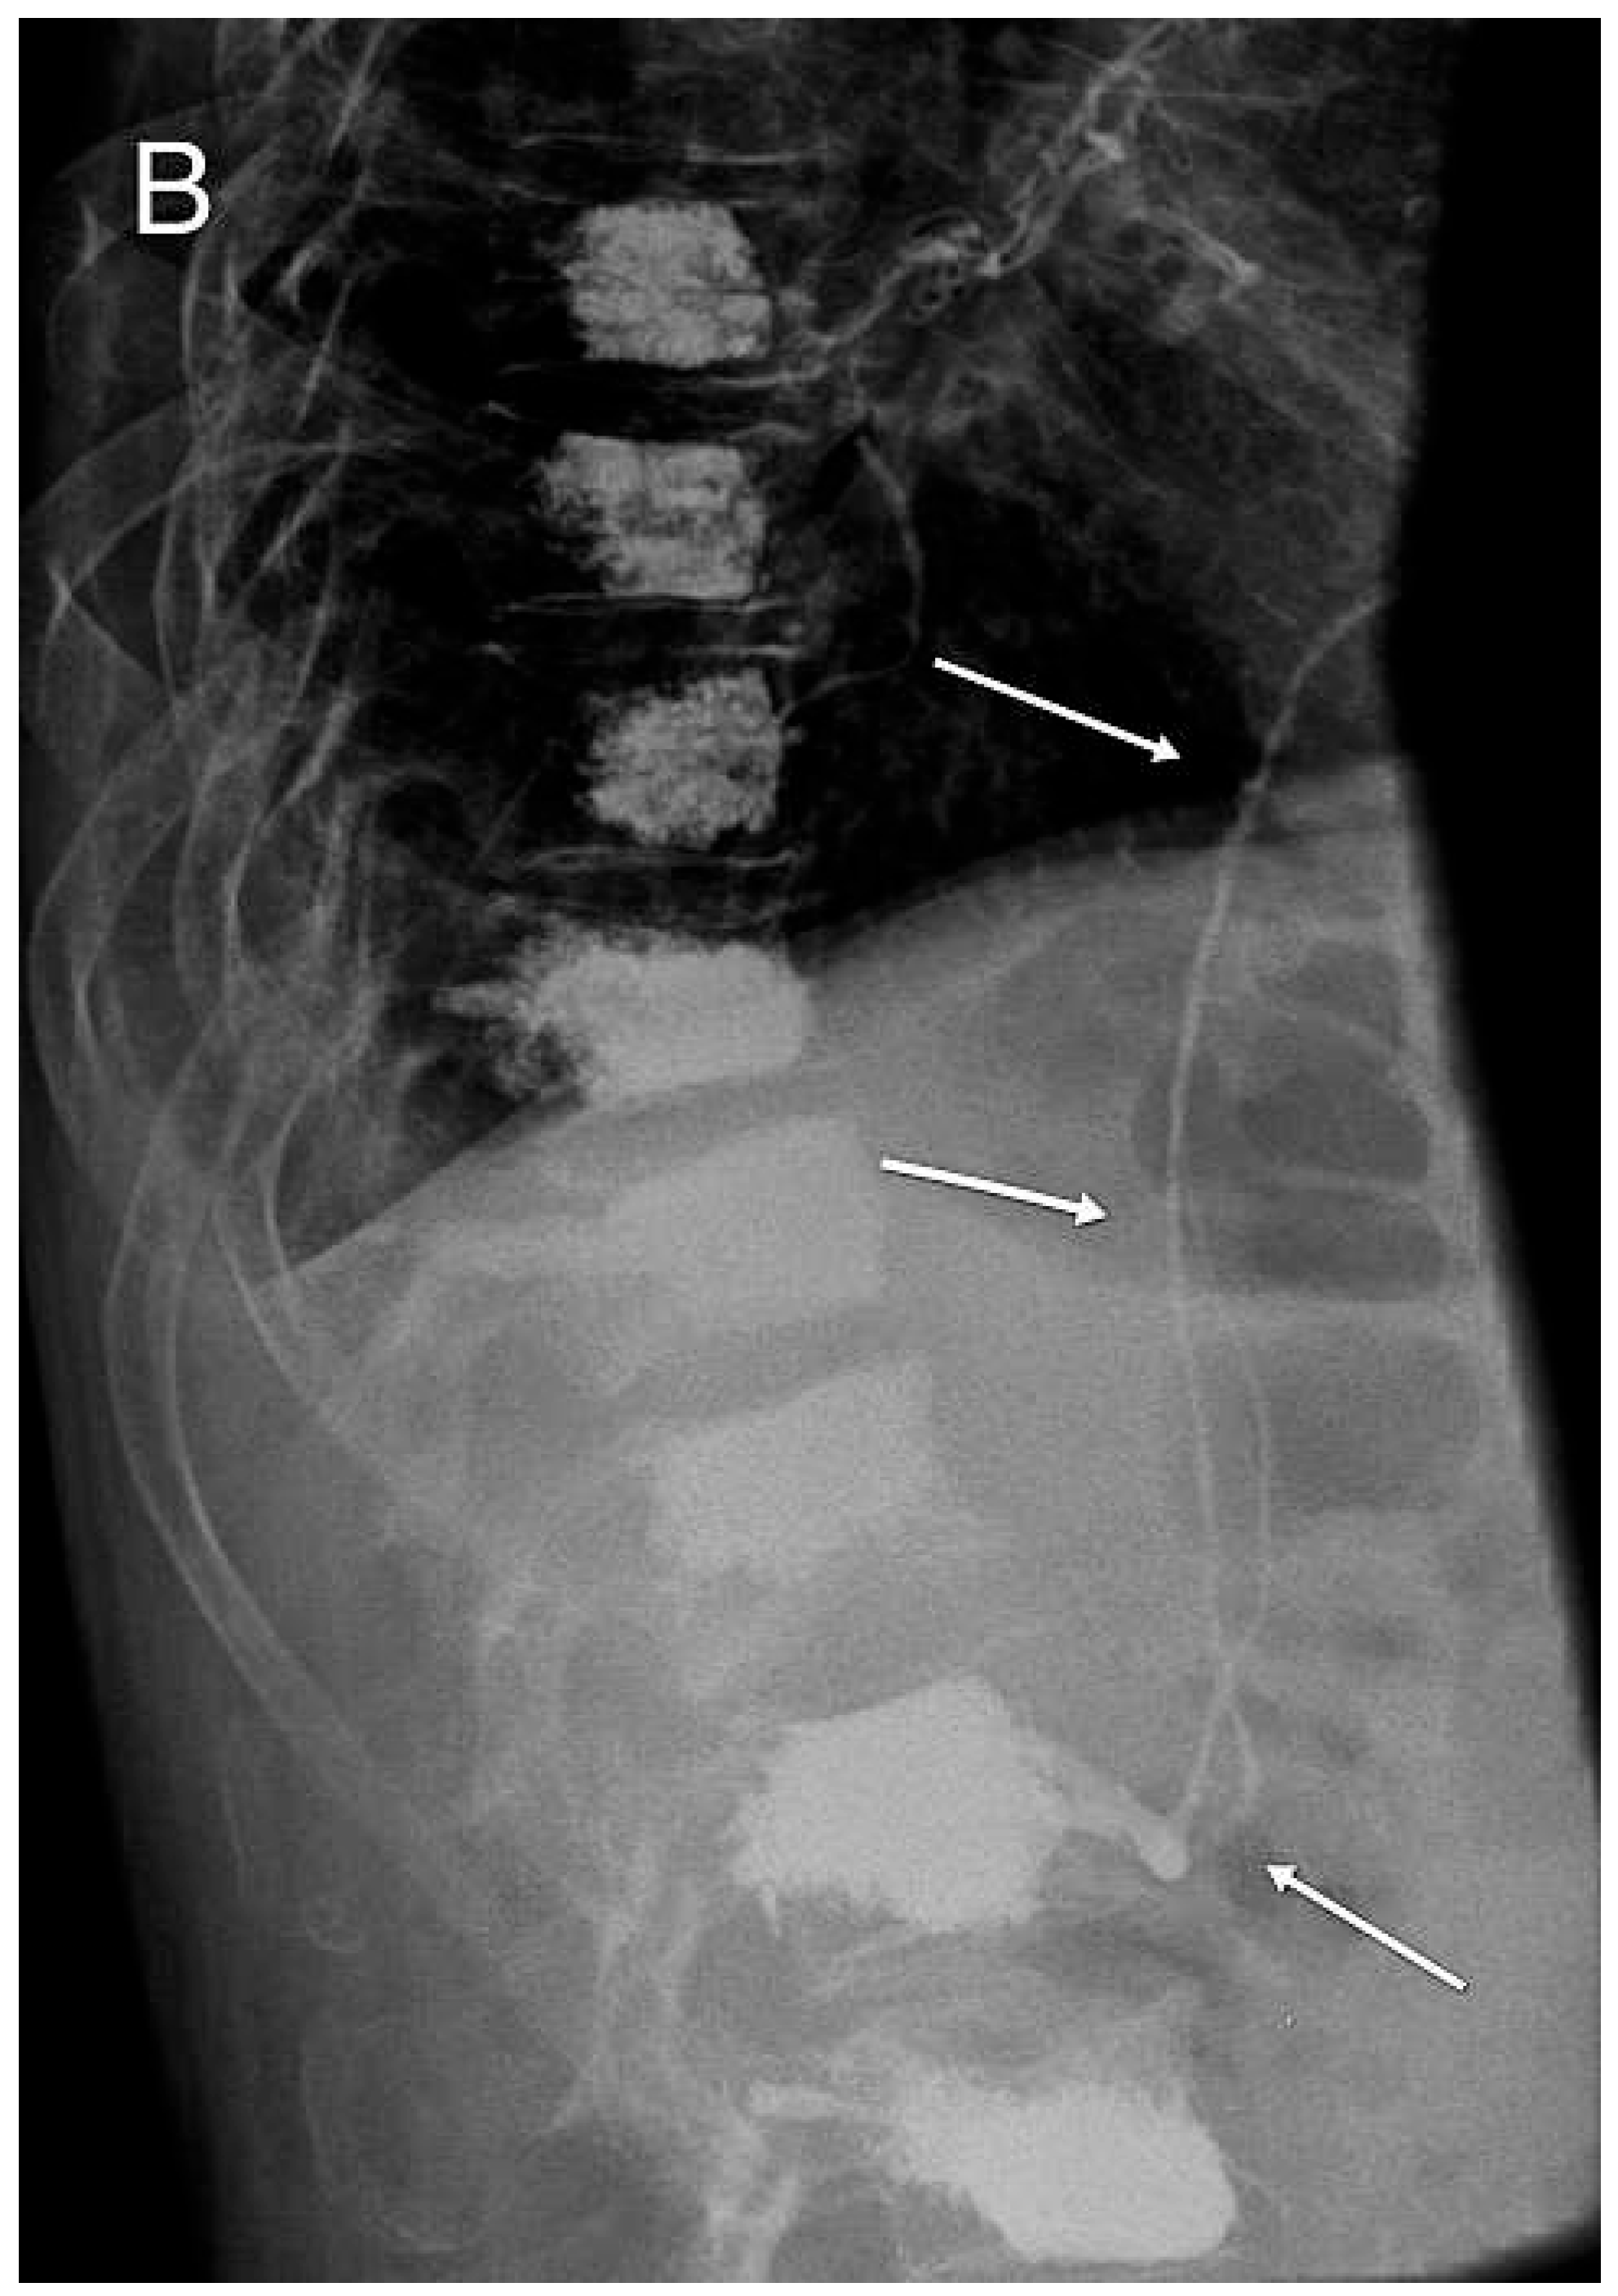

Acrylcement Pulmonary Embolism

Zumsteina, D.; Widmer, F.; Blay, M. Acrylcement Pulmonary Embolism. Cardiovasc. Med. 2013, 16, 95. https://doi.org/10.4414/cvm.2013.00118